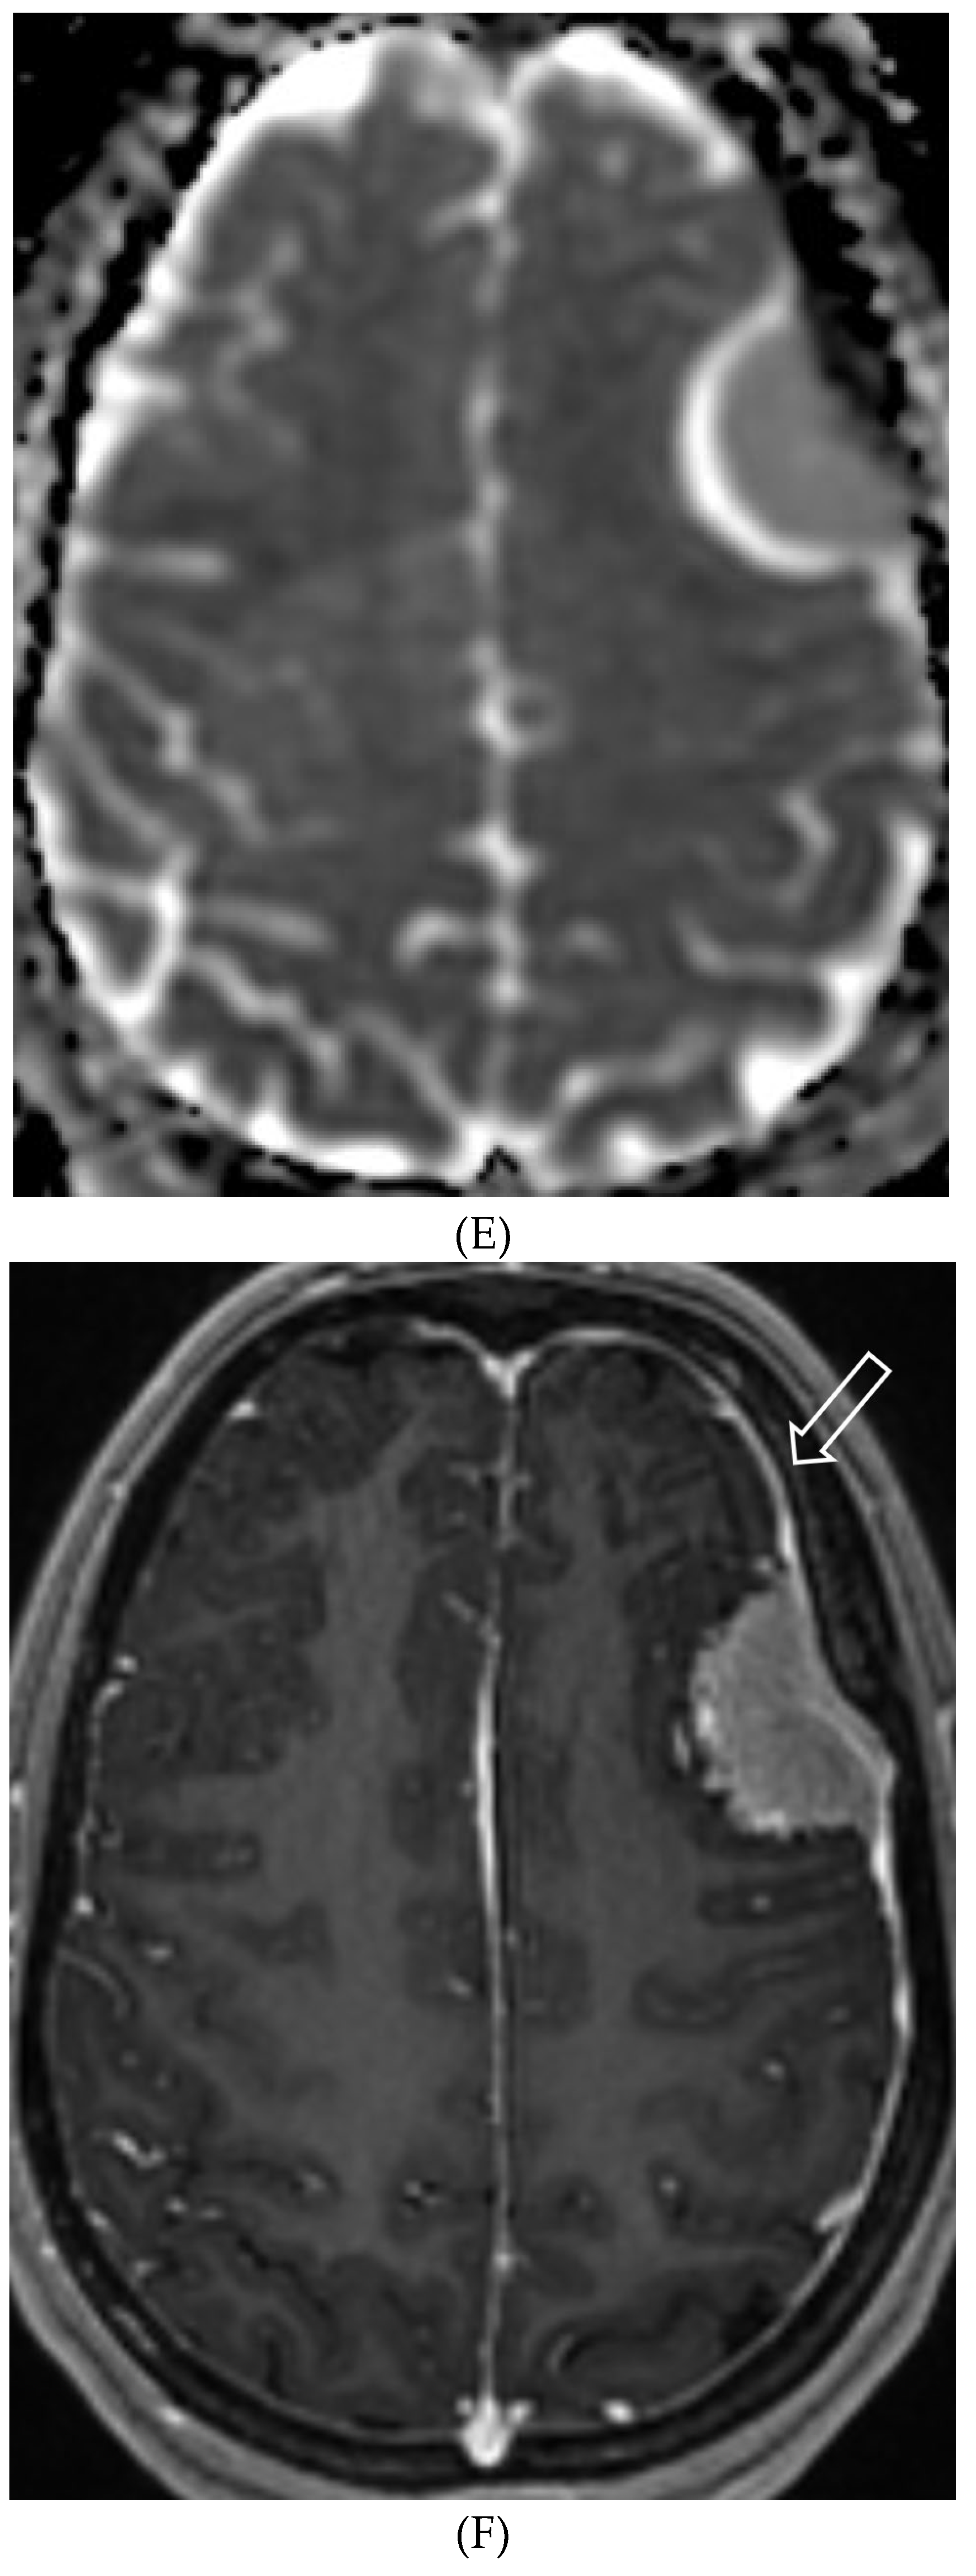

- Liu ZW, Han C, Zhao F, Qiao PG, Wang H, Bao XY, Zhang ZS, Yang WZ, Li DS, Duan L. Collateral Circulation in Moyamoya Disease: A New Grading System. Stroke. 2019 Oct;50(10):2708-2715. Epub 2019 Aug 14. PMID: 31409266. [CrossRef]

- Horie N, Morikawa M, Nozaki A, Hayashi K, Suyama K, Nagata I. "Brush Sign" on susceptibility-weighted MR imaging indicates the severity of moyamoya disease. AJNR Am J Neuroradiol. 2011 Oct;32(9):1697-702. Epub 2011 Jul 28. PMID: 21799039; PMCID: PMC7965393. [CrossRef]

- Ohta T, Tanaka H, Kuroiwa T. Diffuse leptomeningeal enhancement, "ivy sign," in magnetic resonance images of moyamoya disease in childhood: case report. Neurosurgery. 1995 Nov;37(5):1009-12. PMID: 8559324. [CrossRef]

- Maeda M, Tsuchida C. "Ivy sign" on fluid-attenuated inversion-recovery images in childhood moyamoya disease. AJNR Am J Neuroradiol. 1999 Nov-Dec;20(10):1836-8. PMID: 10588105; PMCID: PMC7657767.